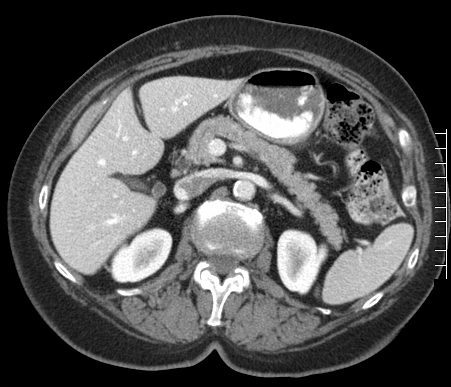

Approach to colorectal cancer

A ct or cat scan is a shortened name for computerized tomography. How does a ct scan work? During a chest ct scan, a person lies on a table as it the contrast dye used in some chest ct scans can cause an allergic reaction, such as hives or trouble breathing.